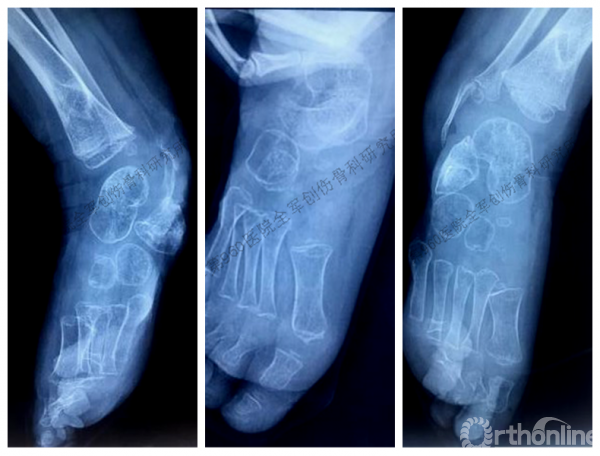

受伤当时X线片

本次术前X线,跟骨仅有前端少许残留